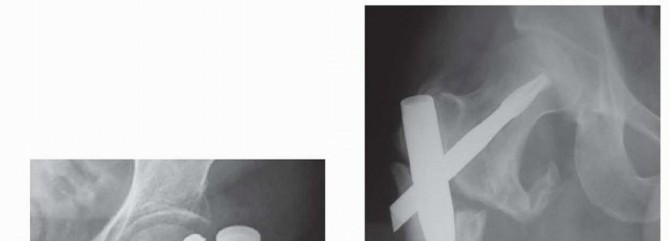

TECH FIG 4 • A. Insertion of reducer through channel reamer, lateral radiographic view. B. Reducer directed guide rod centered on lateral radiograph, avoiding anterior distal cortex. C. Diaphyseal reaming through channel reamer. D. Nail insertion. For trochanteric nail, the surgeon matches the curve of the nail with the proximal femur during initial insertion to minimize hoop stress at entry portal. The nail is rotated into correct position after 30% to 50% insertion. 4. ## Single-Screw or Single-Device Designs (Gamma, Stryker; IMHS, Smith & Nephew; TFN, DePuy Synthes) The center-center wire is inserted to within 5 mm of subchondral bone. Fracture reduction is confirmed and the length to lateral cortex is measured.

--- TECH FIG 5 • A. Gamma nail AP view with lateral trochanteric portal and center-center head screw position. B. Russell-Taylor IIB fracture with short InterTAN nail A C. Lateral view. If compression is desired (usually 5 mm), the surgeon reams for the screw and selects a screw 5 mm shorter than measured. For the TFN, the head is not reamed. The surgeon inserts the head fixation screw or nail to the desired depth; position is confirmed on AP and lateral C-arm views ( TECH FIG 5A). The option of compression and locking of the lag screw with a set screw within the nail is available on selected systems ( TECH FIG 5B,C).